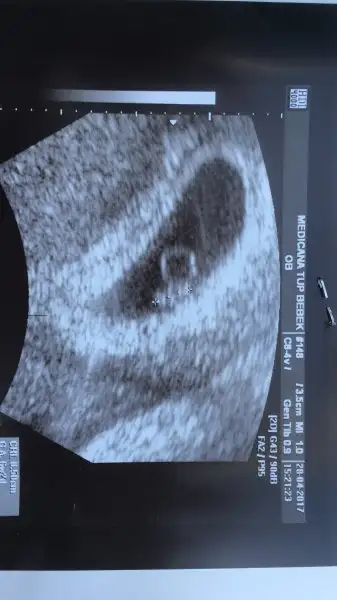

Gözün aydın CNm ben de seni merak ettmiştim:)Selam kızlar Dra gittim bu gün çok şükür kalp atışını çok iyi duyduk bebek 7+2 olması gerek sata göre şu an 6+2 ama kalp atışı da kesede olması gerektiği gibi dedi şükür. Haftaya cuma tekrar bakacak içim rahatladı çok şükür